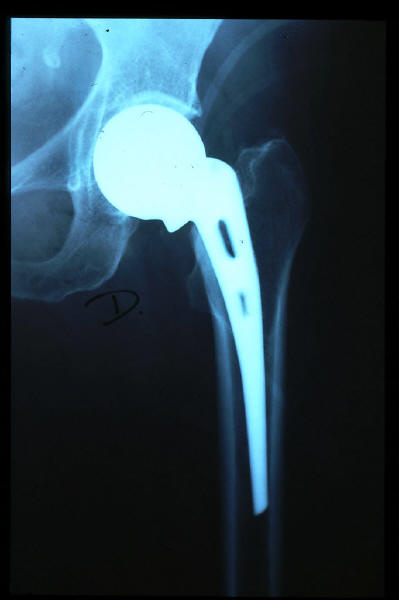

Fractura cuello fémur. Prótesis completa.

Fractura de fémur, prótesis parcial de cadera

Prótesis parcial de cadera

Prótesis de cadera.